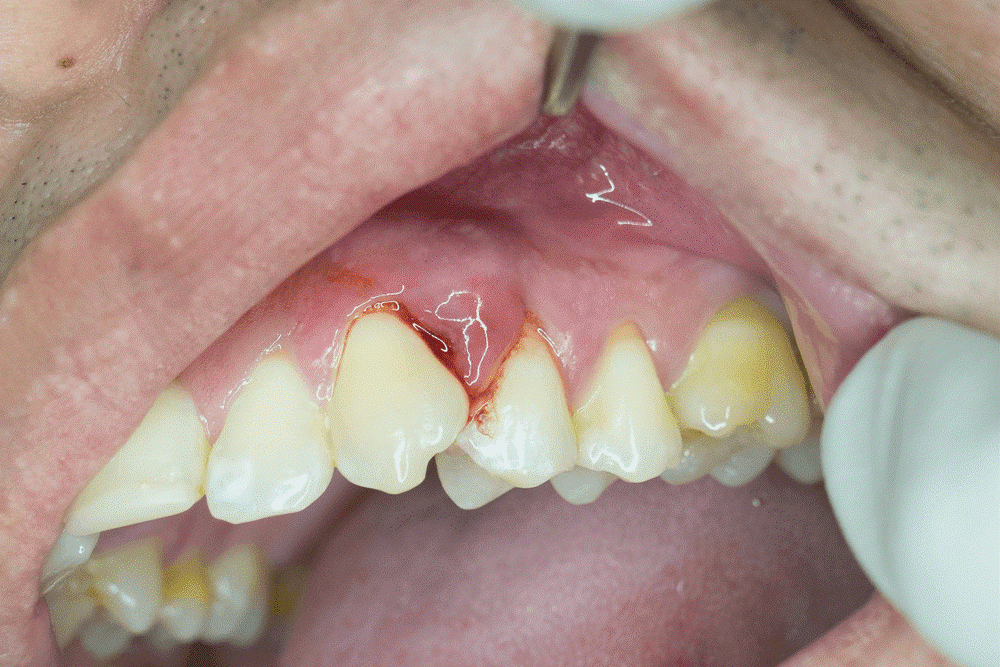

- لثه های متورم و ملتهب

- تخلیه آبسه: در این شیوه دندانپزشکی یک برش کوچک در سطح آبسه ایجاد میکند و با استفاده از محلول های خاص نمکی و ضدعفونی کننده منطقه را پاک میکند.